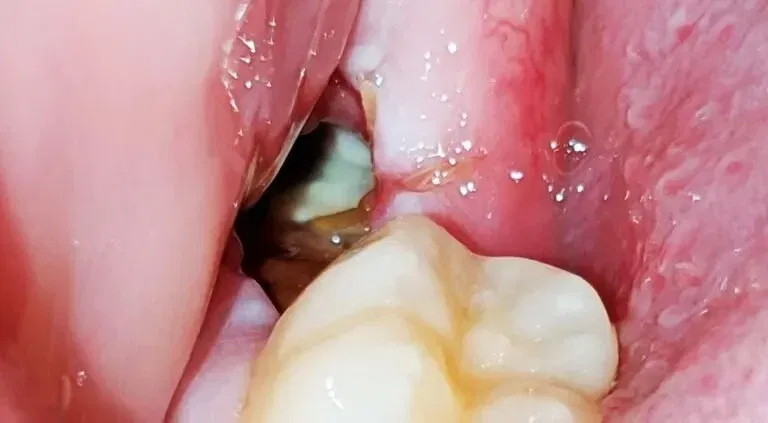

Several variables can affect the duration of your wisdom teeth removal surgery. The position of your wisdom teeth plays a crucial role—if they’re fully erupted and easily accessible, the procedure will be quicker. However, if your wisdom teeth are impacted or positioned at difficult angles, your surgeon will need additional time to safely extract them.

On average, you can expect the procedure to take between 30 minutes to 2 hours. However, your individual circumstances may require more or less time. For instance, if your wisdom teeth are deeply impacted or particularly challenging to access, the process might extend beyond the typical timeframe. Conversely, if your wisdom teeth are fully erupted and straightforward to remove, your surgeon may complete the procedure in under an hour.

Depending on the tooth’s size and position, it may be removed in one piece or sectioned into smaller parts for easier extraction. If the tooth is impacted, your surgeon may need to remove some surrounding bone tissue to safely retrieve it. This is similar to situations involving a broken tooth root still in the gum, where careful extraction is essential.